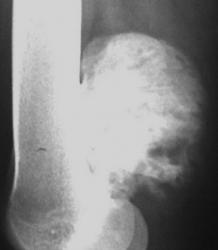

Девушка 23 лет поступила на обследование с диагнозом бурсит левого коленного сустава, из жалоб ограничение механической функции сустава (в виде невозможности полного сгибания) и не сильно беспокоящие боли в ночное время. Объективно в левой подколенной области пальпируется плотное, не смещаемое, овальное образование.

В ОКБ делали рентгенографию ---> Ds: обызвествившаяся гематомаРву и мечу!.

РЕНТГЕНОГРАММА

Изображение        Ну и рентген, вот тока качества плохого, из сотового..

Остеохондрома или остеома.

У меня почему то первые мысли были в пользу экхондромы, но как то развеялись, мне почему то кажется надкостница вообще интактна, ни какой ножки, ни основания не видно. Да и края больно четкие. Хм....

Касательно этого случая, коллеги: я просто рентгенолог и в МРТ - полный валенок... Меня смущает, что по рентгенограмме образование имеет очень высокую плотность - костную или хрящевую (известковую). Насколько я могу судить по МРТ - плотность образования отличается от плотности нормальной кости. Я очень хочу знать мнение специалистов МРТ, какой ткани соответствует плотность образования.

По рентгенограмме я бы сказала, что это хрящевая опухоль, наиболее вероятно - периостальная (юкстакортикальная) хондрома, есть такая редкая форма периферических хондром, когда опухоль расположена на поверхности надкостницы. По рентгену в диф. ряд можно включить параостальную остеосаркому, но по причинам, приведенным выше, думаю - не она.

Спасибо за ваши комментарии коллеги, я в диф. ряд выставил 1)остеохондрому, 2)юкстакортикальную (параоссальную) остеосаркому + реактивный синовит и рекомендовал проведение компьютерной томографии, для уточнения состояния надкостницы и получения более адекватных характеристик плотности образования (всёж образования исходящие из костей удел КТ).

По поводу того что надкостница "вообще интактна" так мне кажется она реагирует на всё это дело.. на представленных аксиальных томограммах в латеральных отделах (L) отмечается её истончение, в медиальных же она утолщена (это ли не реакция?). Ещё заставляет задуматься локальное разрастанание надкостницы видимое на сагиттальных томограммах (указано зеленой стрелкой), уж очень напоминающее периостальный  "козырёк", вот только острый угол открыт в другую сторону по длиннику кости.

Говоря о структуре (всёже для более достоверных характеристик необходимо проведение КТ) то я так же более склонен к тому, что ткань образования преимущественно хрящевая, в целом структура гетерогенная с участками жидкостной интенсивности МР-сигнала линейной формы (зоны кистозной дегенерации) и фрагментами гипоинтенсивными во всех импульсных последовательностях (вероятно обызвествления).

Ага, теперь есть от чего плясать! Давайте порассуждаем, коллега. Есть образование хрящевой плотности, что согласуется с рентгеновской и морфологической картиной. Костной плотности нет, образование не связано с корковым слоем - вычеркиваем параостальную остеосаркому и остеохондрому. Образование связано, возможно исходит из надкостницы, т.е. периостальное по локализации. Есть участки жидкостной плотности, а возможно миксоматоза (ослизнения) или некроза. У нас остается периостальная хондрома, учитывая неоднородность структуры, участки жидкостной плотности, в диф. ряд следует включить хондромиксоидную фиброму, периостальную хондросаркому